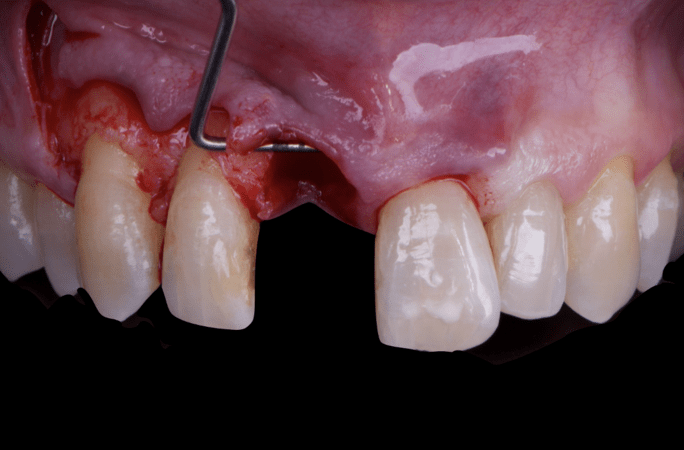

Given the significant buccal defect, guided bone regeneration (GBR) was performed simultaneously. A mixture of autologous bone and creos™ xenogain™ was applied to the defect and covered with a resorbable creos™ membrane to restore ridge width and support the buccal contour. In addition, a connective tissue graft was harvested and placed in the vestibular region to increase the thickness of keratinized mucosa. This combined approach addressed both hard and soft tissue deficiencies, providing the biological foundation for a stable and esthetic outcome.